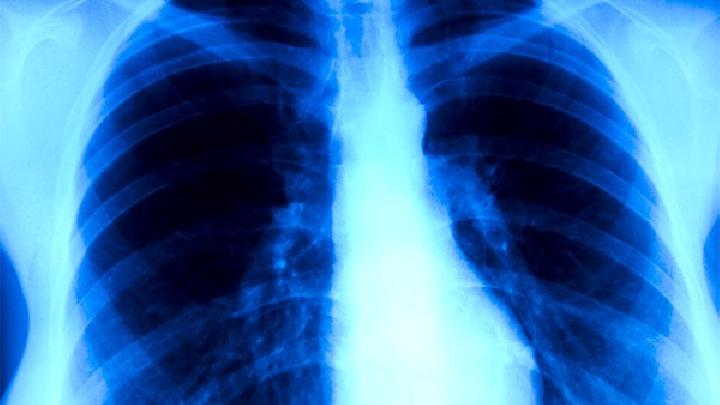

得了肺纤维化严重吗?关于肺纤维化是否严重的问题,是患者都想要了解的,肺纤维化是一种慢性肺部疾病,而且肺纤维化到晚期的危害性是很大的,甚至有死亡的可能性,关键看患者是否能够尽早的进行治疗和护理,具体请看下面的介绍。

肺纤维化的症状是一种原因不明、以弥漫性肺泡炎和肺泡结构紊乱最终导致肺间质纤维化为特征的疾病,按病程有急性、亚急性和慢性之分,所谓特发性肺纤维化综合征属急性型,临床更多见的则是亚急性和慢性型,那么肺纤维化有哪些症状,我们来了解一下。